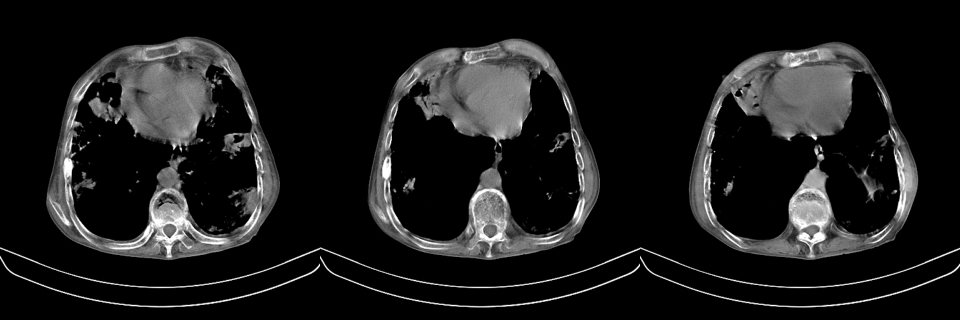

以下是引用mzh123在2007-8-26 19:58:00的发言:[br]两肺弥漫性斑片改变,其中可见大小不等之不规则空洞,结合既往病史还是考虑结核复发及感染。

以下是引用云翔在2007-8-26 20:54:00的发言:[br]这是44岁的肺吗?是否有先天病的基础?干酪性肺炎?